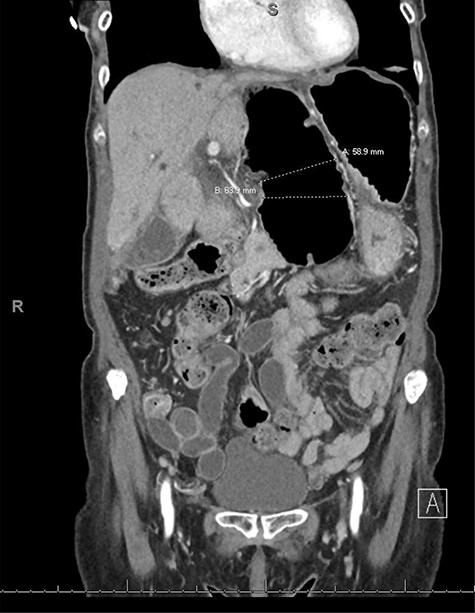

An 80-year-old female with past medical history of Crohn’s disease (diagnosed in 1998 and managed with Adalimumab) and no prior abdominal surgical history who presented with 1-day history of severe epigastric pain associated with nausea and emesis. Her last colonoscopy was 3 years ago (unremarkable), and last Crohn’s flare was a 1 year beforehand. On examination, patient’s abdomen was soft with severe epigastric tenderness and an appreciable bulge. Labs showed normal lactate (1.1) but mild leukocytosis of 12.5 and no other gross lab abnormalities. Patient underwent computed tomography (CT) scan of abdomen and pelvis which showed a transverse colon herniating through the FOW and causing a closed-loop obstruction (Figs. 1–3). Patient was immediately decompressed with a nasogastric tube and was emergently taken to the operating room for a diagnostic laparoscopy. Intraoperatively, the transverse colon was noted to have herniated through the FOW into the lesser sac. The incarcerated transverse colon appeared immensely dilated and hyperemic. With careful traction and gentle counter pressure, the transverse colon was completely reduced from the FOW back into the abdominal cavity. On inspection after reduction, the small and large bowel appeared grossly viable and well-vascularized along with adequate peristalsis. The FOW was closed with 2-0 ethibond running suture by suturing the peritoneum adjacent to the portal triad down to the retroperitoneum just lateral to the inferior vena cava. The patient tolerated the procedure very well and brought to the recovery room in stable condition. Postoperatively, the patient did very well. On postoperative Day 1, the patient was discharged home. Subsequently, the patient was seen in the office on postoperative follow-up Day 7 and was found to be doing well with no complaints.

CT coronal view showing proximal and distal loops of transverse colon are seen in the region of the foramen of Winslow.